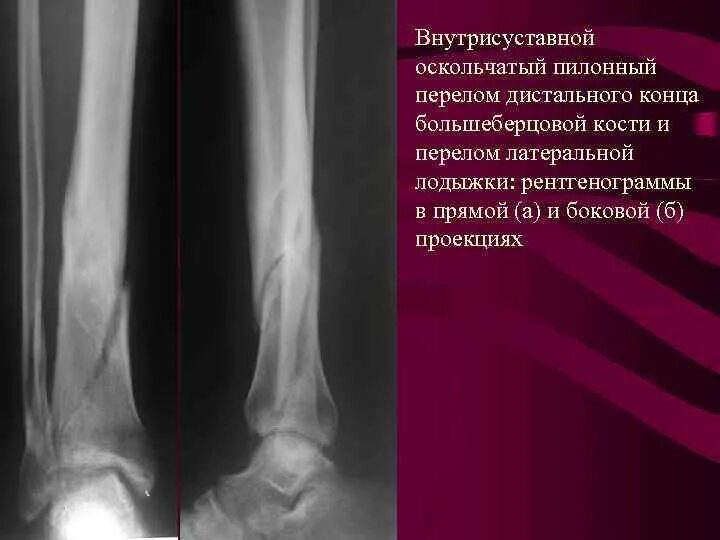

Закрытый оскольчатый перелом со смещением